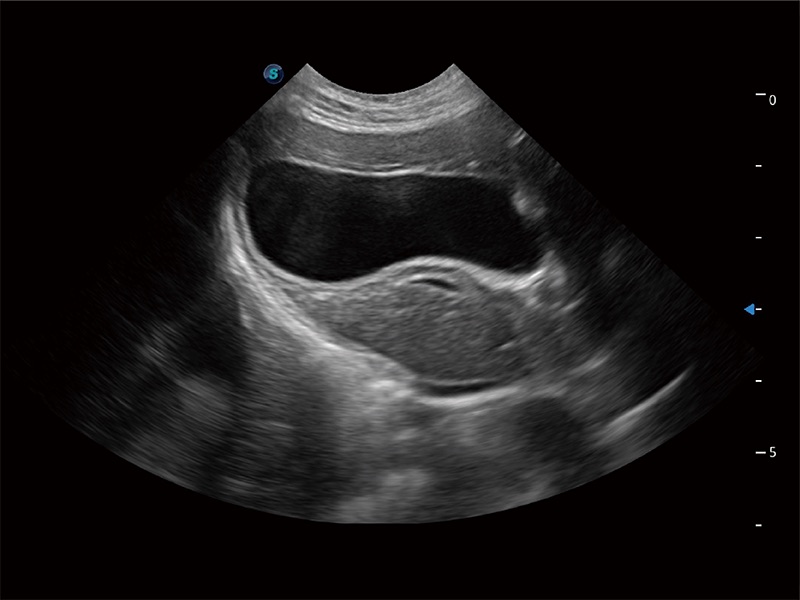

极大提升超低速微细血流的检出能力,同时更精准地滤除软组织和超声信号,为兽用医生提供以往无法通过常规血流获得的疾病诊断信息。